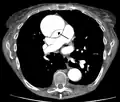

CT with contrast demonstrating aneurysmal dilation and a dissection of the ascending aorta (type A Stanford)

Chest CT with descending (type B Stanford) aortic dissection (red circle)

Type A dissection with pericardial effusion as a result.